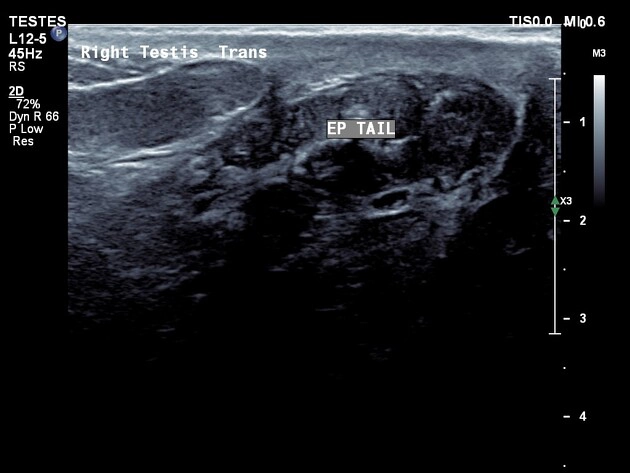

Nang mào tinh (Epididymal cyst)

16/03/2026